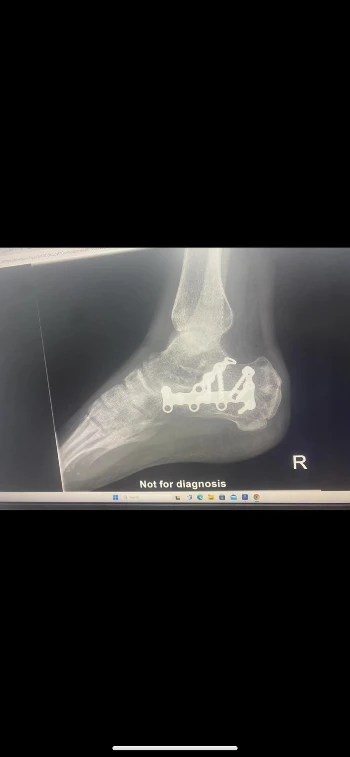

Op 14 augustus 2023 is Dont pijnlijk ten val gekomen door een sprong van 2,5 meter hoog. Hierdoor is het bot van zijn enkel door zijn rechter voet geschoten en zijn voet volledig verbrijzeld. Het medische traject blijft aanslepen. Hij heeft ondertussen al een operatie achter de rug en heeft injecties ontvangen tegen de immense pijn.

Dont woont en werkt ondertussen 2 jaar in Malta. De ernst van zijn verwonding maakte werken quasi onmogelijk en dit in een land waar de ziekteverzekering en medische werkloosheid (uitkering) een vrijwel ongekend gegeven zijn. De kosten van de medische ingrepen zijn dan ook torenhoog. In zijn recuperatie heeft hij geen enkele financiële steun ontvangen van de overheid, dus ook geen uitkering. De kosten hebben zich hierdoor opgestapeld tot 7000 euro.